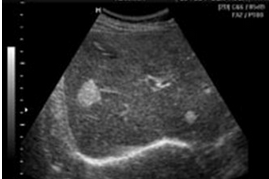

Гиперэхогенные очаги в паренхиме органов (рис. ниже) свидетельствуют о наличии участков обызвествления или разрастании патологической ткани (опухоль, метастаз). Гипоэхогенные участки также указывают на разрастания патологической ткани - опухоль, метастазы (рис. 5), или – на абсцесс. Анэхогенный очаг отличается от гипоэхогенного наличием эффекта так званого «дорсального усиления». Анэхогенная зона всегда обусловлена жидкостным образованием (киста). Киста имеет округлую форму и ровные контуры (рис. 6).

Сонограмма печени. Определяются несколько гипоэхогенных очагов с неровными контурами – метастазы.